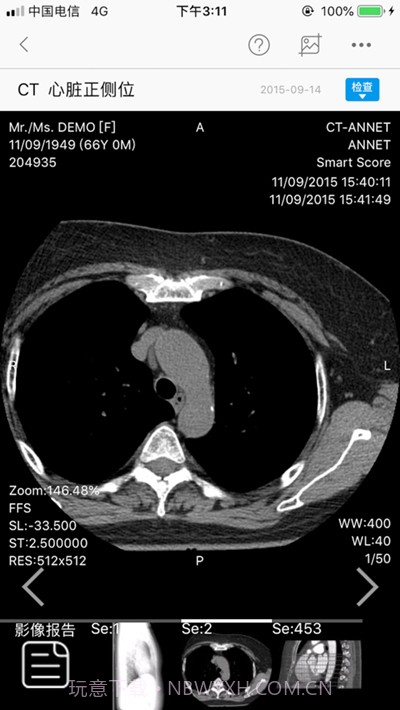

电子病历管理,全面记录患者信息

我感觉中山移动医生真的是个宝藏应用!作为一名医务工作者,这个APP让我在日常看病和管理病历的时候省下了很多时间。它的在线问诊功能超级方便,随时随地都能与患者沟通,语音视频聊天功能更是让医患之间的交流变得无比流畅。电子病历管理简直是我的得力助手,它帮助我全面记录患者信息,还能多媒体记录,让病历更生动。简洁的界面和高效的数据同步功能,让我再也不怕找不到资料,这可是医生们提升效率、改善服务质量的神器啊!